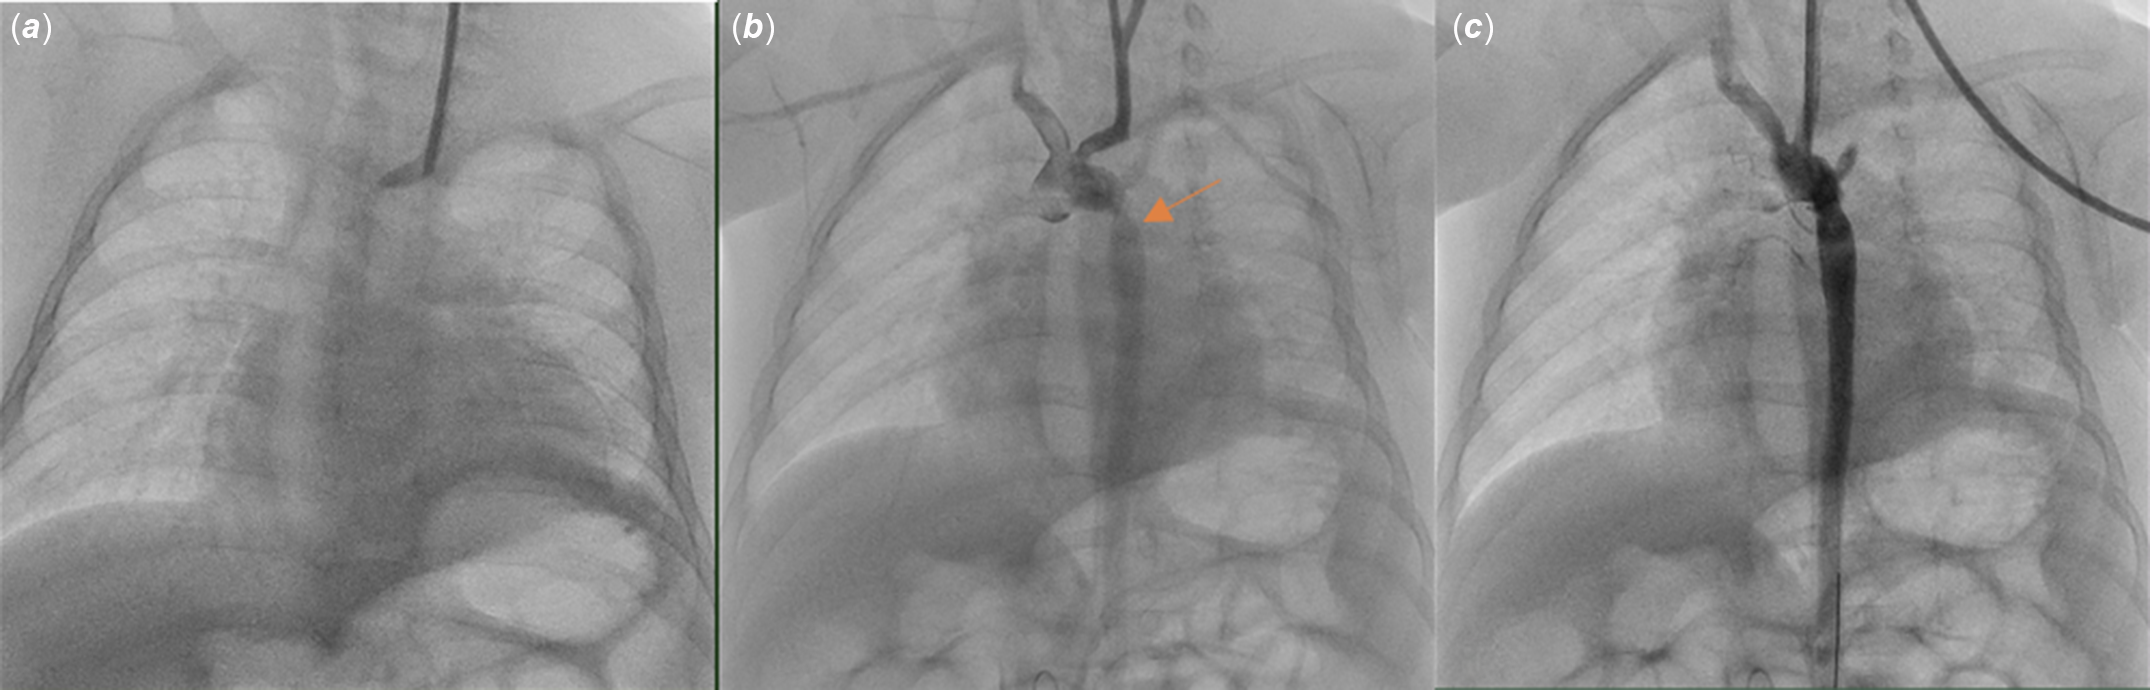

A 6-month-old girl was admitted to the hospital for evaluation for coarctation balloon angioplasty. In medical history, the patient was operated on due to aortopulmonary window, interrupted aortic arch, and aortic coarctation when she was 12 days old. Balloon angioplasty was performed for recoarctation 1 month later. Then, she underwent a second operation due to left phrenic nerve palsy. The patient was referred for evaluation due to recoarctation. On physical examination, she weighed 4.3 kg and revealed scars from previous surgeries around the left thoracotomy and left subcostal region. The femoral pulses were weak. A 2/6 systolic ejection murmur was heard in the interscapular region. On the echocardiogram, there were left ventricular hypertrophy and diastolic flow pattern in descending aorta. It was decided to perform a balloon coarctation angioplasty for the recurrence of the aortic coarctation. In the catheter laboratory, efforts to find access from femoral and axillary arteries were unsuccessful. Left common carotid artery access was performed by using an 18-gauge needle and 0.035-inch wire under ultrasound guidance, and a 4F sheath was inserted. Intravenous heparin 30 unit per kilogram was admitted. There were no complications during the procedure (Fig 1). The patient was discharged from the hospital one day after the procedure. After 10 days, the family noticed a prominent mass on the left side of the patient’s neck. The patient was called in for control. During the patient’s examination, a 2 × 2 cm pulsating mass on the left side of the neck, with no signs of infection on the skin, was noted (Fig 2). On ultrasound, a 2 × 2 cm pseudoaneurysm was detected adjacent to the left common carotid artery (Fig 3). To better assess the location. of the pseudoaneurysm, a CT angiography was performed. CT revealed a 3 × 3 cm pseudoaneurysm with a 3 mm connection with the left common carotid artery, located 2 cm below the bifurcation. Due to the pseudoaneurysm, the trachea and surrounding structures were noted to be shifted to the right side (Fig 4). The management was discussed with the department of interventional radiology. A stent graft was not suitable since the patient was an infant. Even the pseudoaneurysm neck was narrow, percutaneous thrombin injection still had a risk of distal emboli, and it was not possible to insert a filter into common carotid artery due to unattainable femoral access. With the department of cardiovascular surgery, it was decided upon to move forward with a surgical treatment plan. During the operation, considering the pseudoaneurysm sac’s growth direction, an incision was made lateral to the right sternocleidomastoid muscle. Sternocleidomastoid was excluded laterally, and the sac was partially exposed with a meticulous dissection. Proximal and distal parts of the carotid artery were identified and clamped after heparinisation. The pseudoaneurysm sac was excised, and the coagulum was removed. 1–2 mm needle hole on carotid artery was localised and closed with separated stitches (Fig 5). The clamps were removed, and the blood flow was re-established. The patient was extubated in the operating room and transferred to the paediatric ICU without any complications. The repeat ultrasound on the post-operative fourth day was normal, and the patient was discharged without any neurologic problems.

Figure 1. 4F sheath was placed in the left common carotid artery under ultrasound guidance in the catheterisation laboratory (A). The orange arrow indicates the region of severe coarctation in the descending aorta (B). Enlargement of the coarctation area after balloon angioplasty (C).